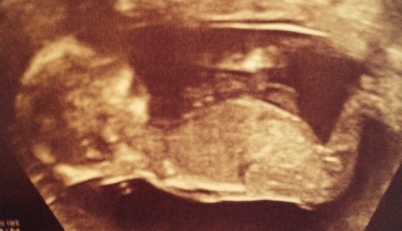

The scan was taken at 14wks, 4 days.

If it is visible, I would welcome your opinions.

I don't think the nub is showing. Plus after 14 weeks I'm pretty sure it doesn't apply anymore:( I think you'd need a potty shot at this point.

Looks like a penis and ballsack to me, but I agree, a potty shot would be better.